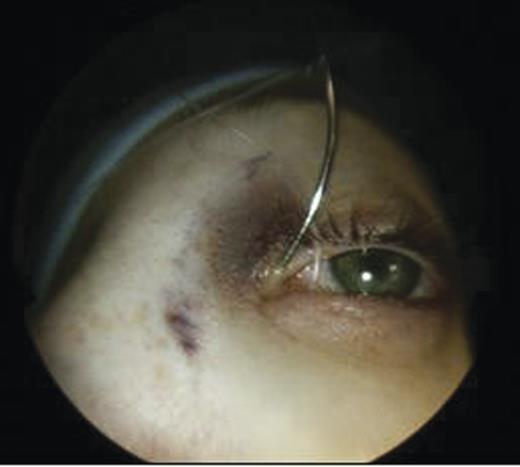

Clinical examination revealed a small cystic swelling in her left medial canthus (Fig. 1). There was no discharge on pressure, mild tenderness was elicited and the swelling was not compressible. The rest of the eye examination was normal with a visual acuity of 6/6 in both eyes.

An MRI scan of the orbits showed a well-defined, thin-walled 22 × 16 mm cyst medial to the left orbit containing fatty/proteinaceous material, which was lying within and mildly expanding the left ethmoid air cells (Figs 1–3).